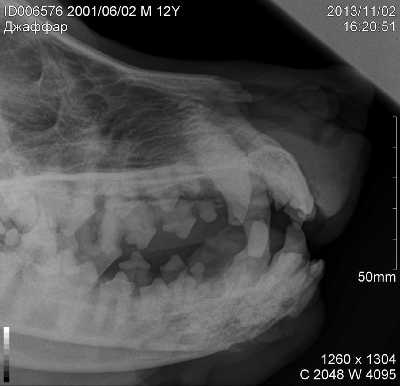

При индуктивных одонтогенных опухолях клетки формируют твердые зубные ткани, которые легко можно идентифицировать на рентгеновских снимках.

Наиболее распространенные локализации — десны и слизистая губ, щеки, но возможна также другая локализация (на нёбе, тыльной поверхности языка). При поражениях десен часто повреждаются зубы, и обычно наблюдаются инвазии в кости.

Остеосаркома полости рта развивается в основном у собак средних и крупных пород и, как правило, в среднем или старшем возрасте. Остеосаркома чаще встречается в нижней челюсти и реже в верхней . Саркому следует дифференцировать от остеомиелита, туберкулеза и кистозной дегенерации кости челюсти.

При опухолях, затрагивающих костную ткань ,основным методом диагностики является рентгенографическое исследование, которое покажет размер и характер развития опухоли.Недифференцированные опухоли ротовой полости у собак часто обнаруживаются у крупных пород в возрасте между 6 и 22 месяцами. Они несвойственны молодым особям, но иногда такое тоже может произойти. Один из видов ротовой опухоли — недифференцированная злокачественная опухоль ротовой полости, такая опухоль не может быть распознана простым биопсическим анализом.